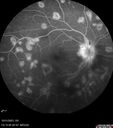

Serpiginous choroiditis in the right eye132 views68 year old female with spots in vision in the right eye for 2 months. She has a history of MS. The vision is 20/32 in both eyes. She was treated with high dose steroids and transitioned to methotrexate and the right eye quieted down.     (0 votes)

68 year old female - In the right eye, the vision is always blurry. There is a big spot off to the side that is always dark. She has a lot of floaters in both eyes some are dark and some are light. These started bothering her a few months ago. She does not usually get headaches and she has been getting headaches starting about 2 weeks ago that are medium severe and sometimes make her want to lie down.

VA 20/32 OU, IOP 17,18

Right eye had mild vitreous cells

Patient admitted to hospital for possible cerebral vasculitis – exhaustively ruled out (MRI, LP)

Labs: CBC, CMP, Quant TB, ACE, Lysozyme, FTA-ABS normal

High dose steroids given in hospital then transitioned to oral steroids and then transitioned to Methotrexate

VA still 20/23 OU – No active uveitis